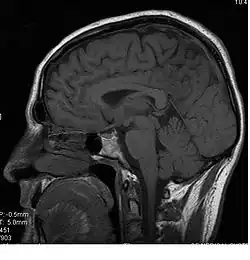

Image du corps calleux en coupe sagittale.

Le corps calleux (ou corpus callosum) est une commissure (moyen d'union entre deux parties) transversale du cerveau présente chez les mammifères placentaires[1]. C’est un faisceau d'axones (fibre nerveuse qui correspond au prolongement long, mince et cylindrique du corps cellulaire d'un neurone) interconnectant les deux hémisphères cérébraux. C'est la plus importante commissure du cerveau, car elle relie les huit lobes du cerveau entre eux (lobes frontaux, temporaux, pariétaux et occipitaux gauche et droit). Le corps calleux assure donc le transfert d'informations entre les deux hémisphères et ainsi leur coordination. Les autres commissures sont le fornix, le cingulum et la commissure blanche antérieure.